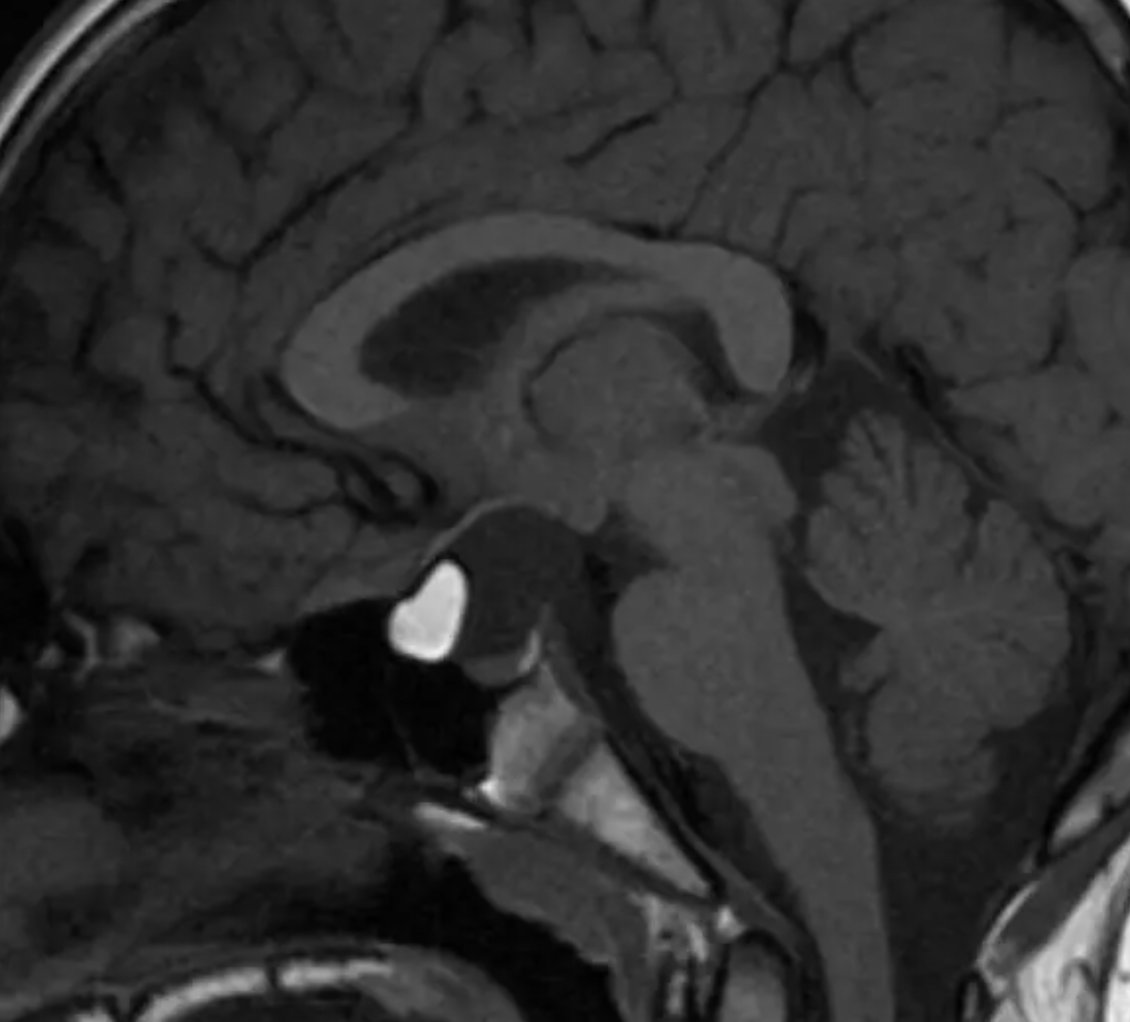

Do you see the lesion here? Hint - it is a T______. Final read: ow.ly/h2Rv50NxH4z ... #medicine #meded